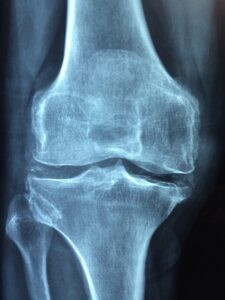

زندگی استئوپنی و پوکی استخوان: چگونه از شکستگیهای استخوانی جلوگیری کنیم؟ پیام جوان: استئوپنی به کاهش تراکم استخوان اشاره دارد که هنوز به اندازهای نیست که به پوکی استخوان تبدیل شود. Read More 2025-01-31

زندگی شناسایی علائم اولیه پوکی استخوان: آنچه باید بدانید پیام جوان: اگرچه علائم پوکی استخوان در اوایل مشخص نیست، اما برخی علائم نشان میدهند که استخوان های شما دارند Read More 2024-11-07

زندگی بررسی روشهایی برای کمک به افزایش تراکم استخوانها پیام جوان: کاهش تراکم استخوانها به این معنی است که فرد در معرض خطر پوکی استخوان به عنوان یک بیماری Read More 2024-04-10

راه های تشخیص ابتلا به پوکی استخوان در بدن پیام جوان: پوکی استخوان یک بیماری نامرئی محسوب میشود؛ چراکه تا زمانی که یک استخوان نشکند، علامتی از خود بروز Read More 2022-12-21